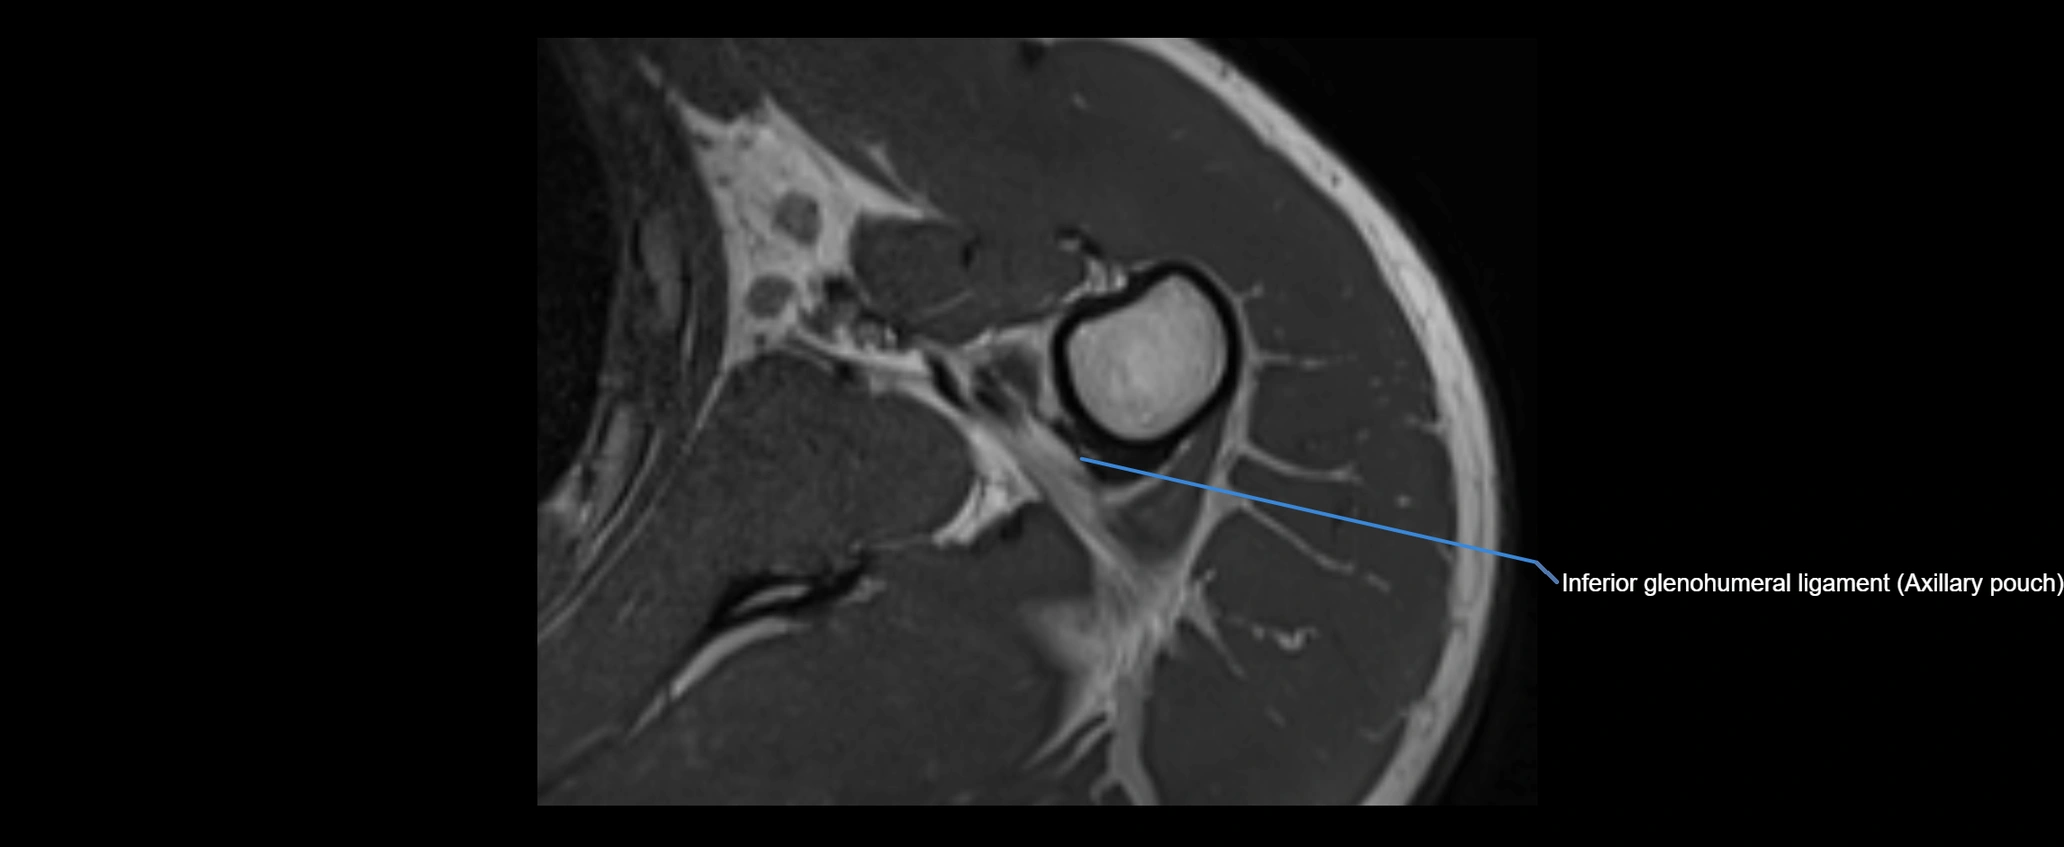

CT image

image

MRI Appearance

• T2-weighted images:

• Proton Density Fat-Saturated (PD FS):